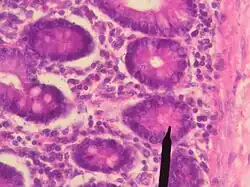

Paneth-Zelle

Paneth-Zellen, auch als Paneth-Körnerzellen bezeichnet, sind merokrine Drüsenzellen, die apikal stark eosinophile Granula enthalten und im Epithel am Grund der Dünndarmkrypten, aber auch im Magen und im Mastdarm auftreten. Aufgabe der Paneth-Zellen ist die Sekretion von Lysozymen, Peptidasen, Laktoferrin und Defensinen. Sie sind somit u. a. für die lokale Immunabwehr verantwortlich. Benannt sind sie nach dem österreichischen Physiologen Joseph Paneth (1857–1890).

- Paneth'sche Körnerzellen mit rot granuliertem Zytoplasma im histologischen Präparat